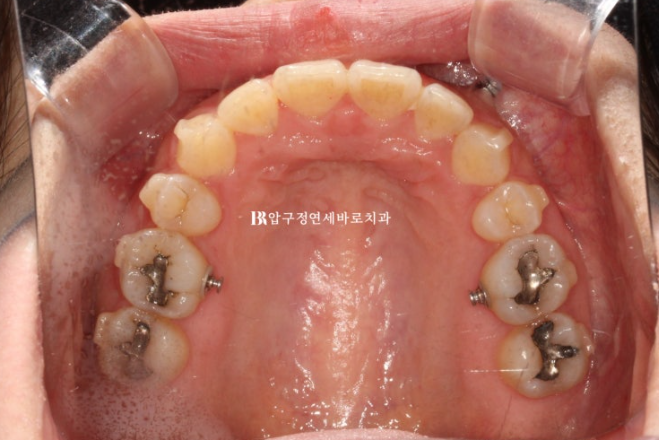

위 작은어금니 두 개를 발치하고 인비절라인 교정 치료에 들어갑니다.

22.09

작은어금니를 발치한 지 일주일째가 된 날 인비절라인 첫번째 장치를 끼기 시작한 날 사진입니다.

이때부터 거미스마일을 적극적으로 해소하기 위해서 앞니에 미니스크류를 심었고 고무줄을 함께 걸기 시작합니다.

23.07

재제작시 발치공간은 절반정도 남은 상황이였습니다.